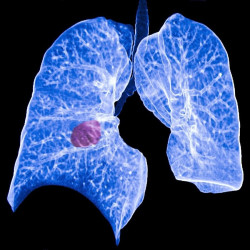

Obtienen nuevos conocimientos sobre la biología de los tumores de pulmón y posibles dianas farmacológicas

Los investigadores han desarrollado el mayor y más completo mapa molecular hasta la fecha del subtipo de cáncer de pulmón carcinoma de células escamosas de pulmón. Su trabajo reúne datos proteómicos, transcriptómicos y genómicos en una visión proteogenómica detallada que ha revelado posibles nuevas dianas farmacológicas, vías de regulación inmunitaria que podrían ayudar al cáncer a evadir las inmunoterapias e incluso un nuevo subtipo molecular, según publican en la revista `Cell`.